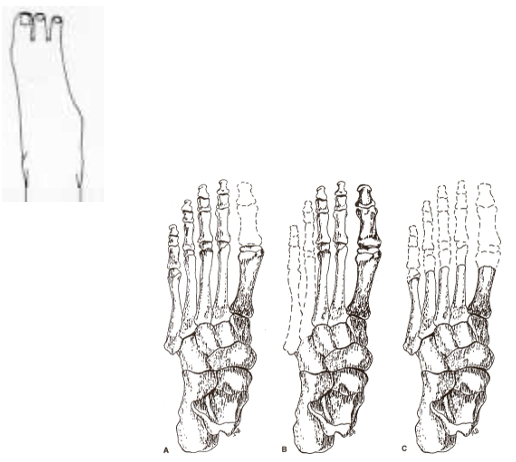

___________ is a partial foot amputation where there is disarticulation of the midtarsal joint

calcaneus; talus

a chopart amputation preserves the _____________ and ____________ bones

lisfranc

___________ is a partial foot amputation where there is disarticulation of the tarsometatarsal joint

transmetatarsal

___________ is a partial foot amputation that is performed through mid-/proximal MT shaft

a ___________ amputation is a longitudinal amputation of one or more metatarsals or toes

a ______________ amputation involves the amputation/disarticulation of one or more toes